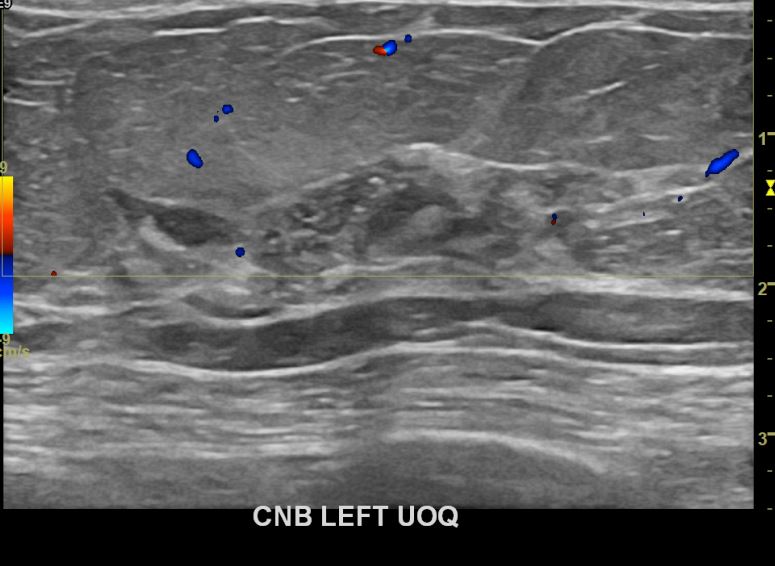

아산유외과개원후 667번째 유방암진단

상기환자 외부검사상 이상소견으로 내원하신 60대여성으로 좌측에 의심스러운혹 조직검사시행해 유방암 진단되었습니다